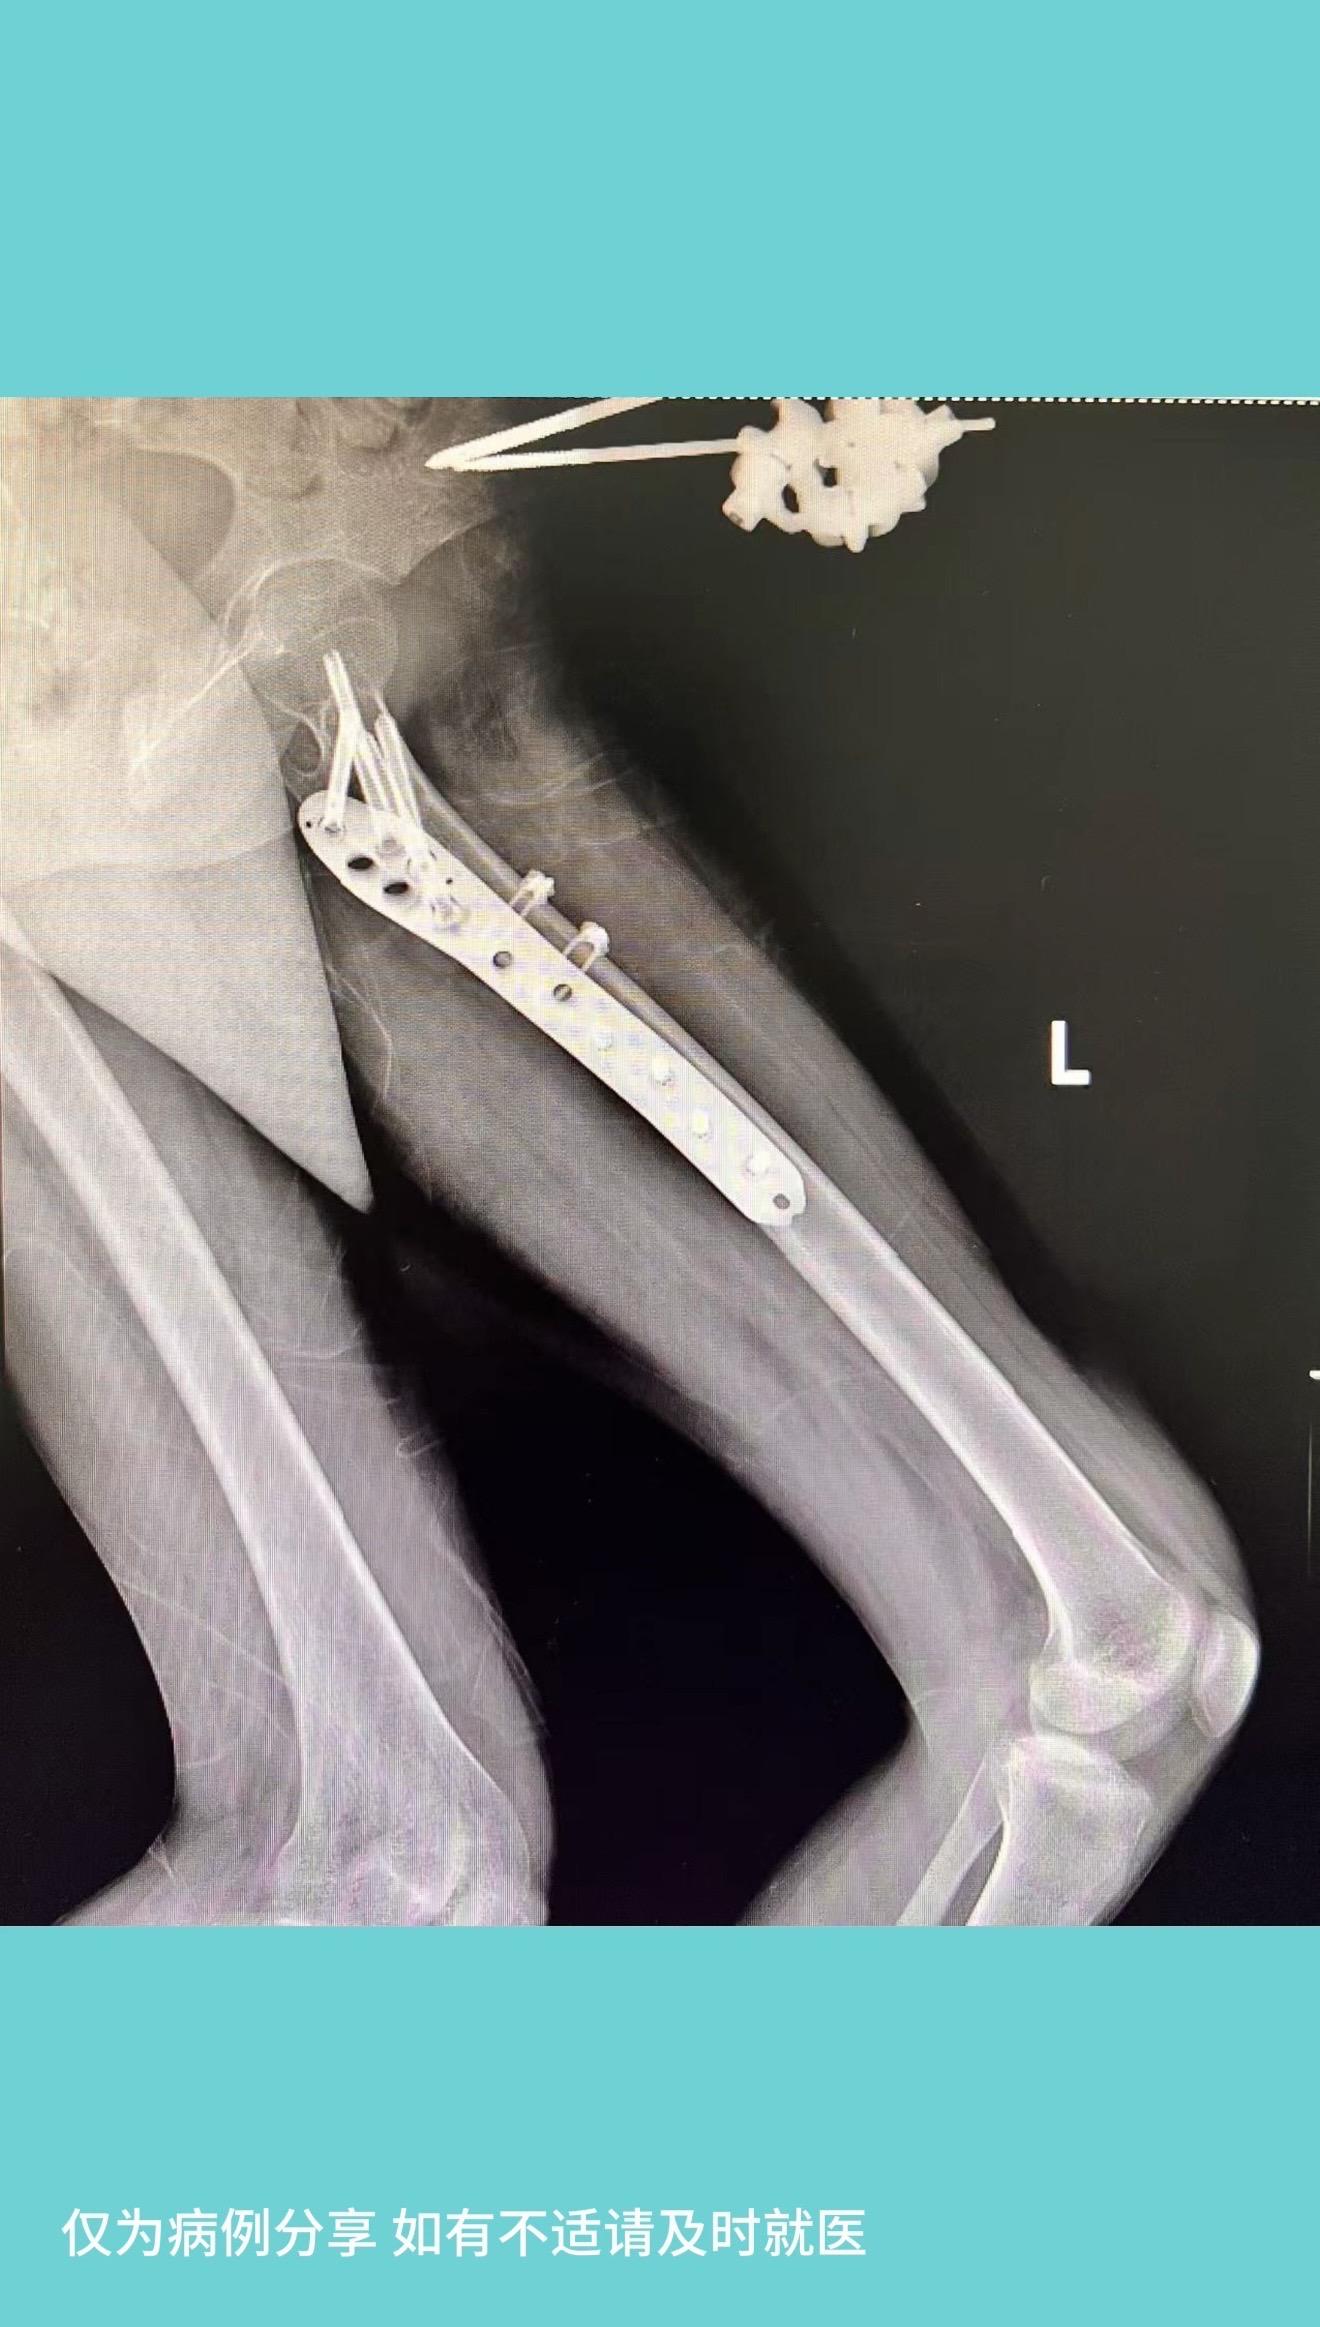

女孩因家人管教,被限制外出,竟“奇思妙想”,仿电影情节,拿一根较细绳子从7楼家中窗户“下楼”,绳子下降到3楼时断裂,摔成重伤。入院后积极治疗,生命体征稳定后,手术治疗,各部位骨折复位满意。左下肢肌力恢复至4级。